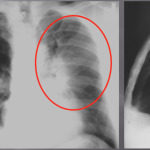

LEFT UPPER LOBE ATELECTASIS

The archive below organizes different examples of a left upper lobe atelectasis. It will really be the anatomical location of the finding that will help diagnosis this SPECIFIC subtype of atelectasis. Click on the thumbnails below to view the archive.

COMPLETE ATELECTASIS

This archive below organizes different examples of complete atelectasis. This will result in a complete white out of the affected lung. Make sure to review the page discussing this radiological finding of complete lung “white out” called hemithorax opacification. Click on the thumbnails below to view the archive.